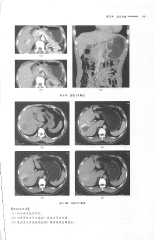

Page 201 - 医学影像诊断学